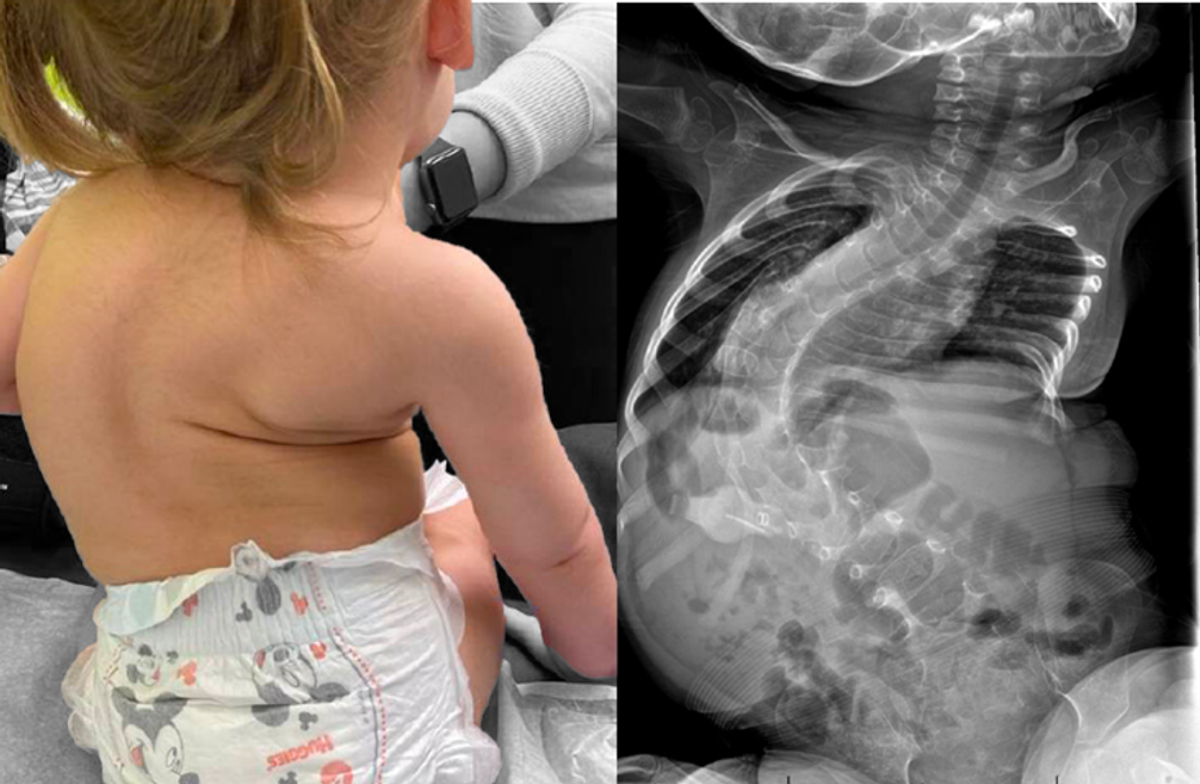

To get Spinraza into motor neurons, the drug needs to be injected directly into the spinal column by lumbar puncture. Unpleasant at the best of times, this can be particularly challenging in older children and adults living with the disease, as spinal curvature is common. It also needs to be administered regularly: up to six injections in the first year of treatment at a cost of £75,000 per injection, and three each year after that.